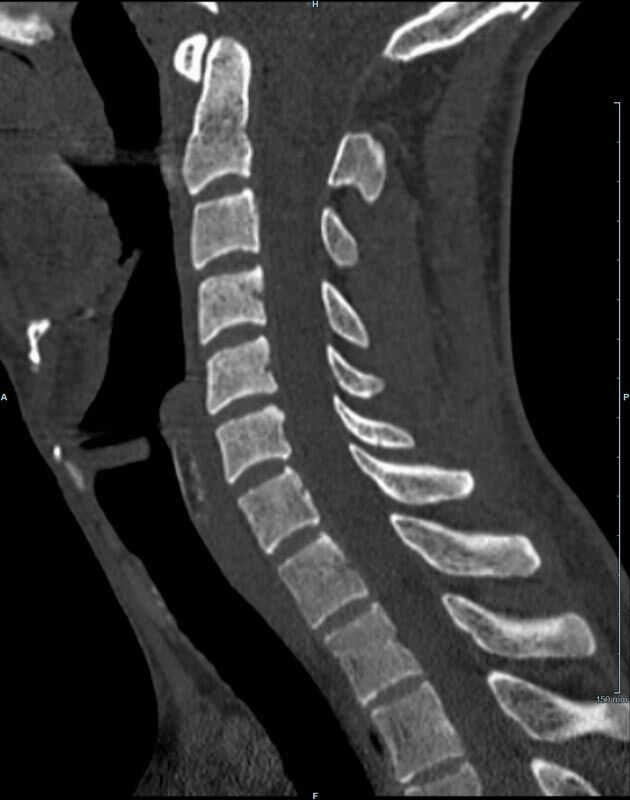

Wirbelsäule

• Darstellung von Frakturen, Tumoren und Bandscheibenveränderungen